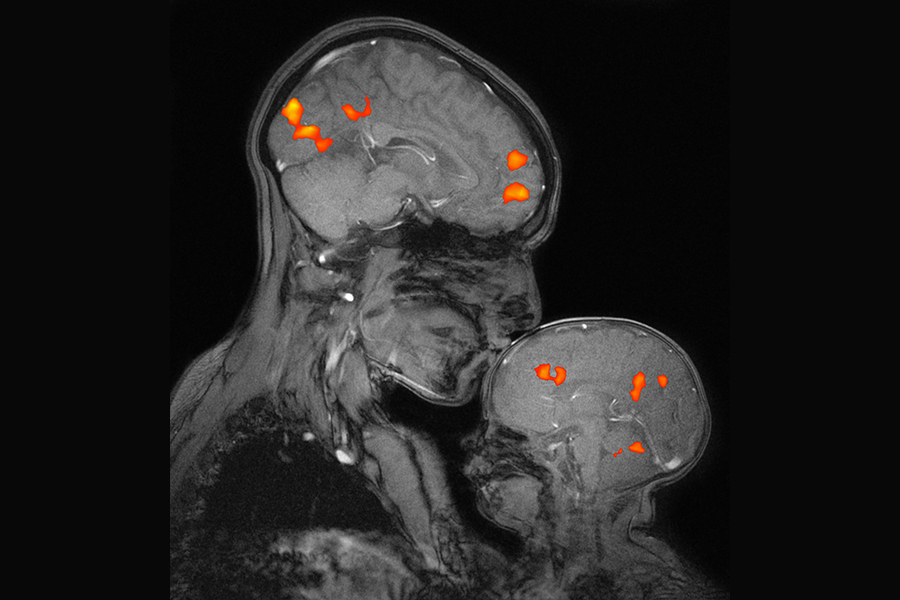

Desimone highlighted the institute’s recent discoveries, including the development of the CRISPR genome-editing system, which has culminated in the world’s first CRISPR gene therapy approved for humans — a remarkable achievement that is ushering in a new era of transformative medicine. In other milestones, McGovern researchers developed the first prosthetic limb fully controlled by the body’s nervous system; a flexible probe that taps into gut-brain communication; an expansion microscopy technique that paves the way for biology labs around the world to perform nanoscale imaging; and advanced computational models that demonstrate how we see, hear, use language, and even think about what others are thinking. Equally transformative has been the McGovern Institute’s work in neuroimaging, uncovering the architecture of human thought and establishing markers that signal the early emergence of mental illness, before symptoms even appear.